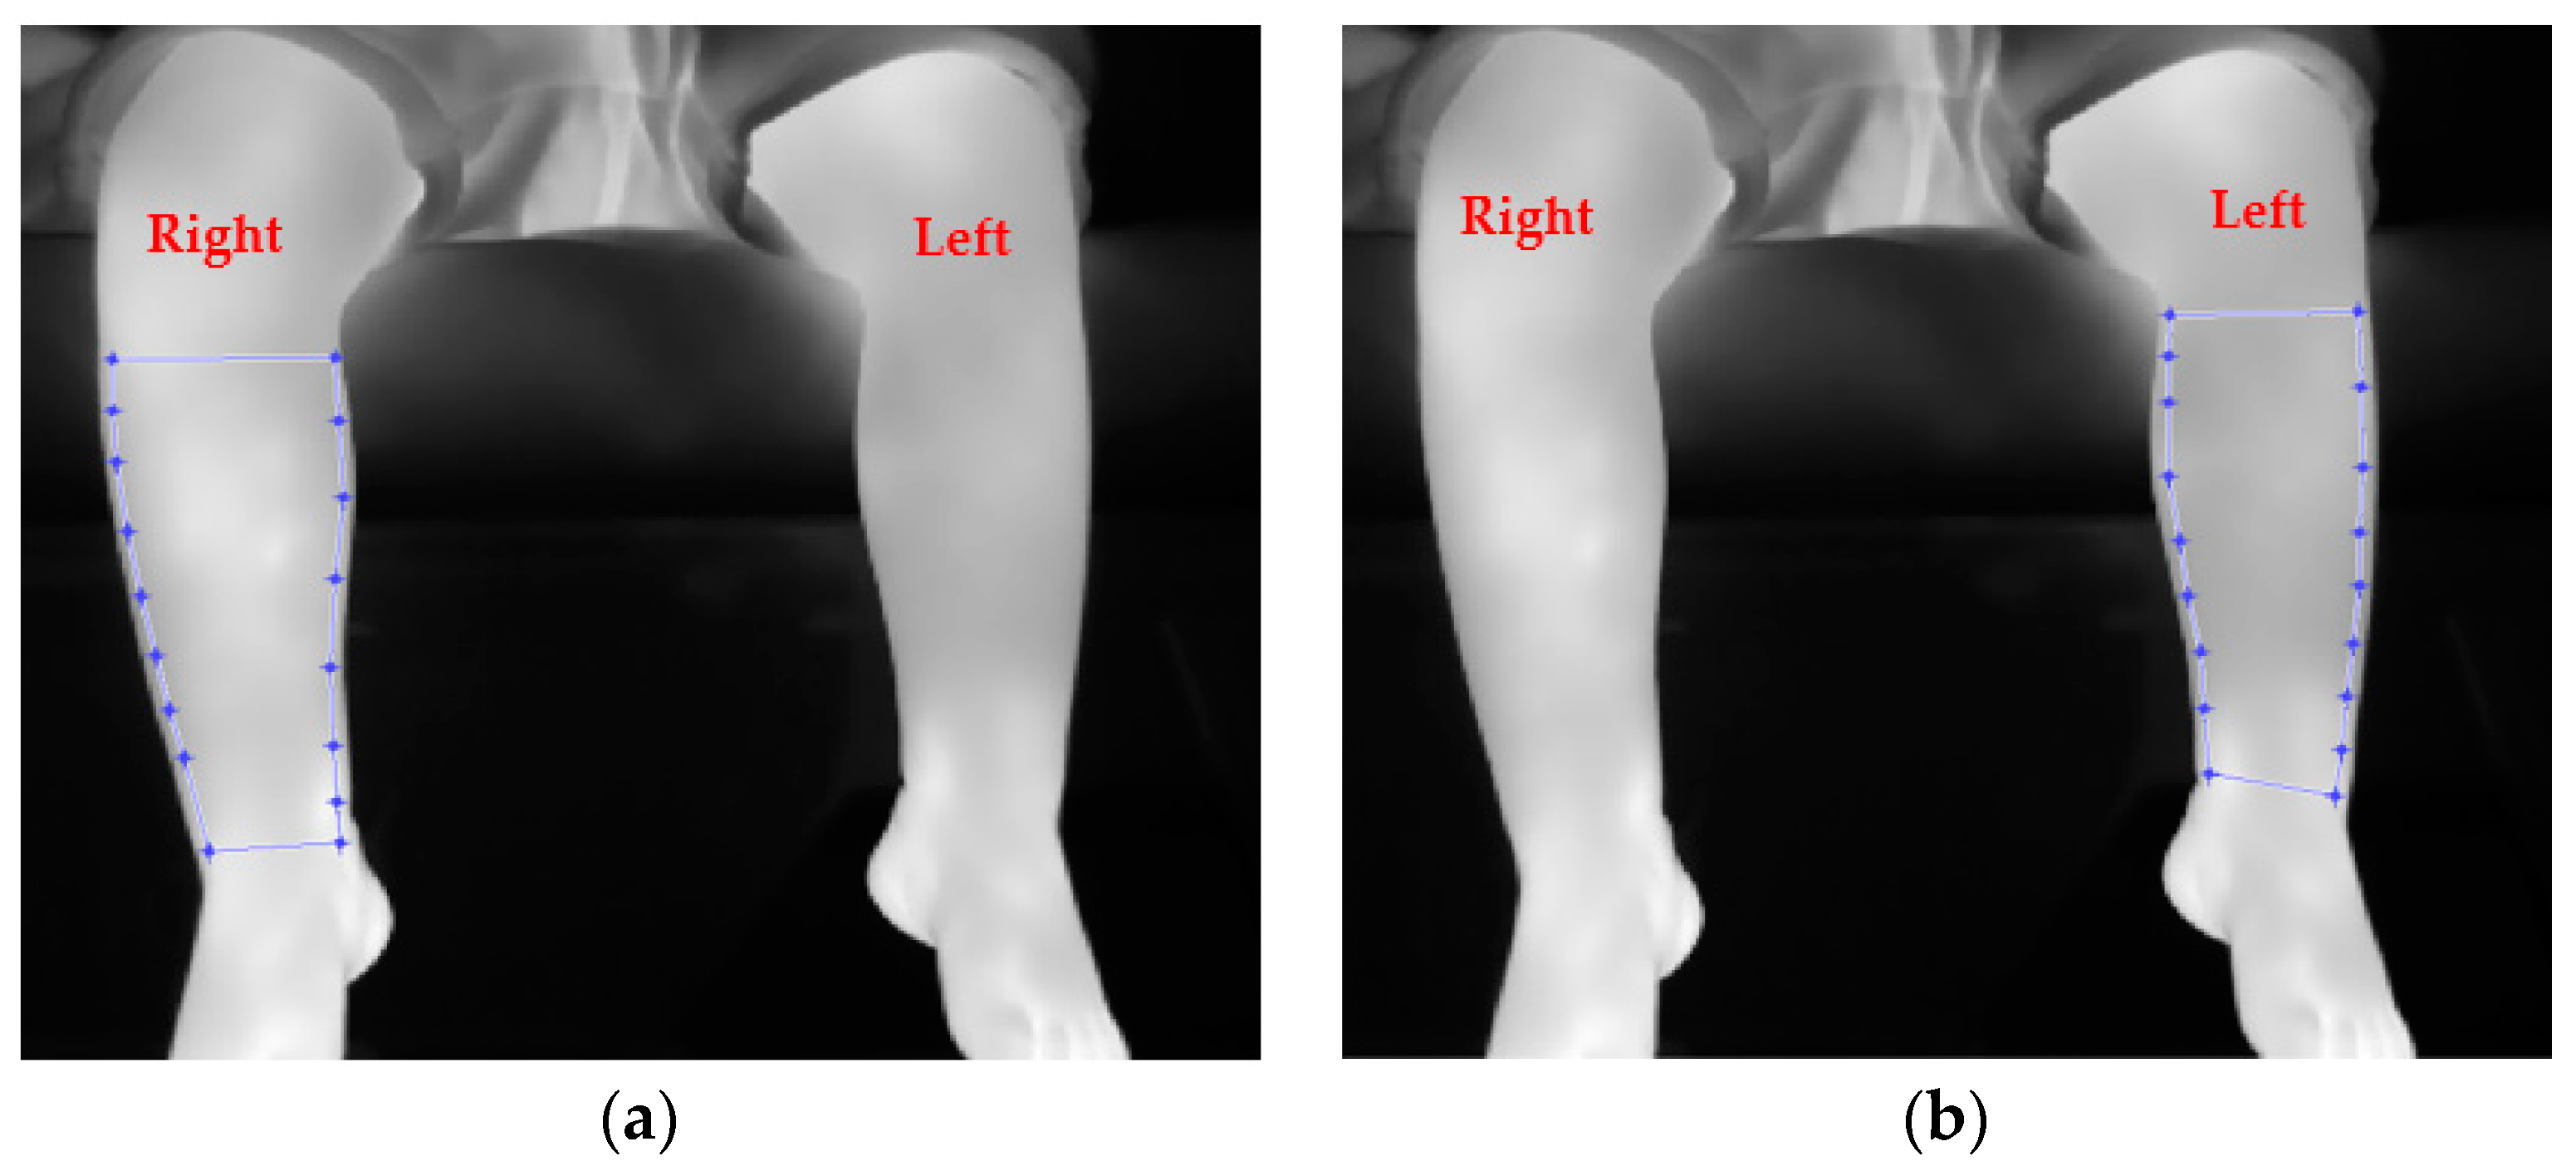

A typical infrared thermal image of a participant with toddler’s fracture is shown in Figure 1. This participant was a 14-month male with a toddler’s fracture of his right leg. The fracture was not detected by x-ray radiography on the first attendance. The injured leg was put into a cast and the child underwent another x-ray on the second visit 10 days later. It was then confirmed as a toddler’s fracture (non-displaced transvers right proximal tibial fracture). The infrared thermal image of the right leg was relatively warmer (brighter colour) as compared with the uninjured left leg. Although visual inspection of an infrared image may highlight temperature anomalies associated with an injury, image and data analysis are still required for a conclusive interpretation [14, 15].

Figure 2. An example of infrared image for a participant diagnosed by x-ray to have a toddler’s fracture of right tibia. (a) and (b) show the cropped regions of interest for the legs.